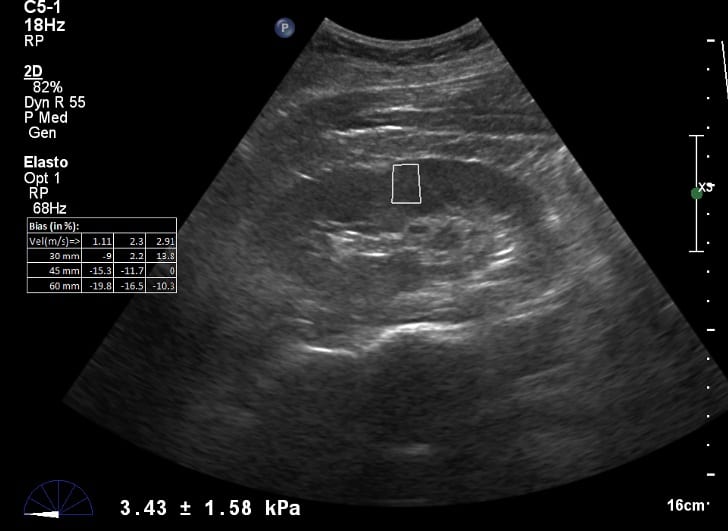

The most common and aggressive type of renal cell carcinoma is the clear cell type. Ultrasound Elastography Is A Quick And Non Invasive Way To Spot Kidney Failure Physics World

Ultrasound Elastography Is A Quick And Non Invasive Way To Spot Kidney Failure Physics World from physicsworld.com